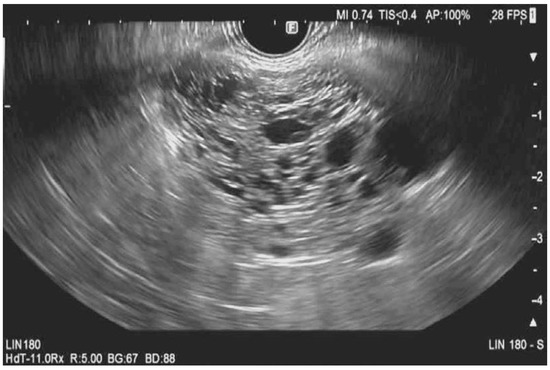

Contrast-Harmonic Mode Endoscopic Ultrasound